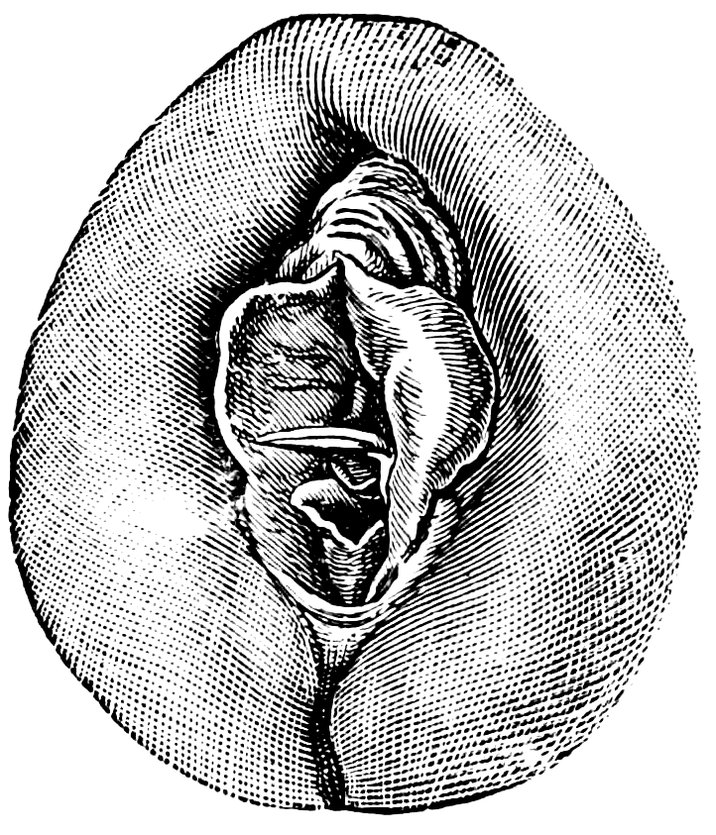

| 12. | Female external genital organs of a virgin | 54 |

| 13. | The external genital organs of a virgin | 55 |

| 48. | The female pudendum, or vulva, with the labia majora | 204 |

| 49. | Vestibule of the vagina, with the labia minora or nymphæ, etc | 205 |